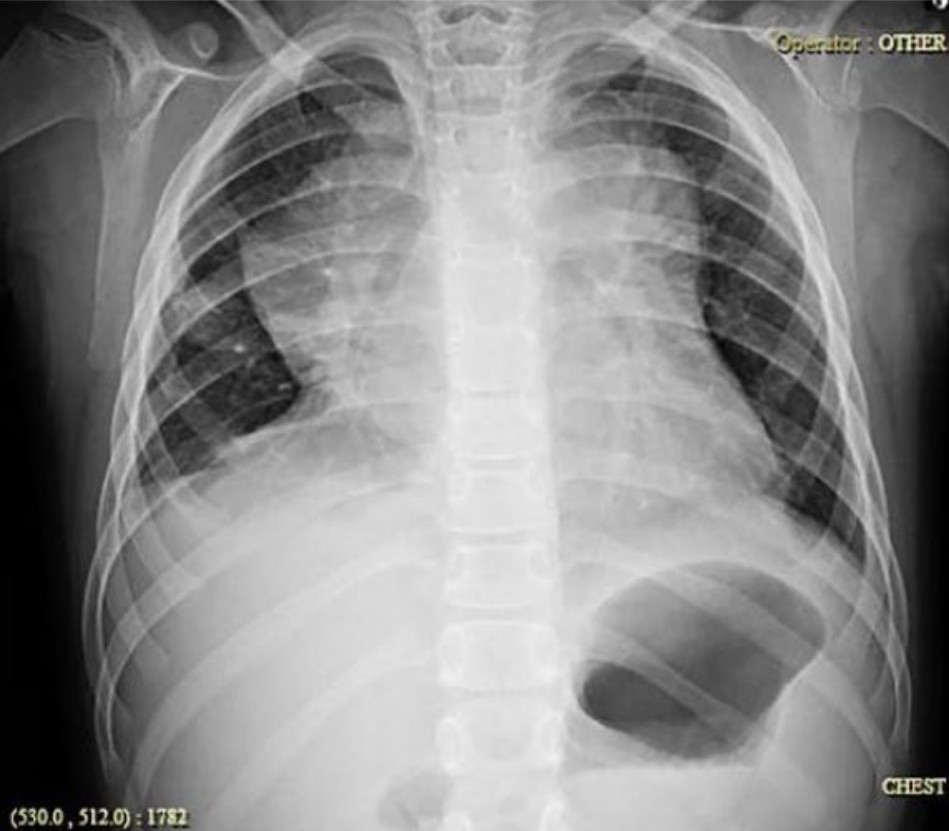

Chest pain in sickle cell disease

A 25-year-old man with sickle cell disease presents with non-productive cough, severe central chest pain and hypoxia. Vitals are as …